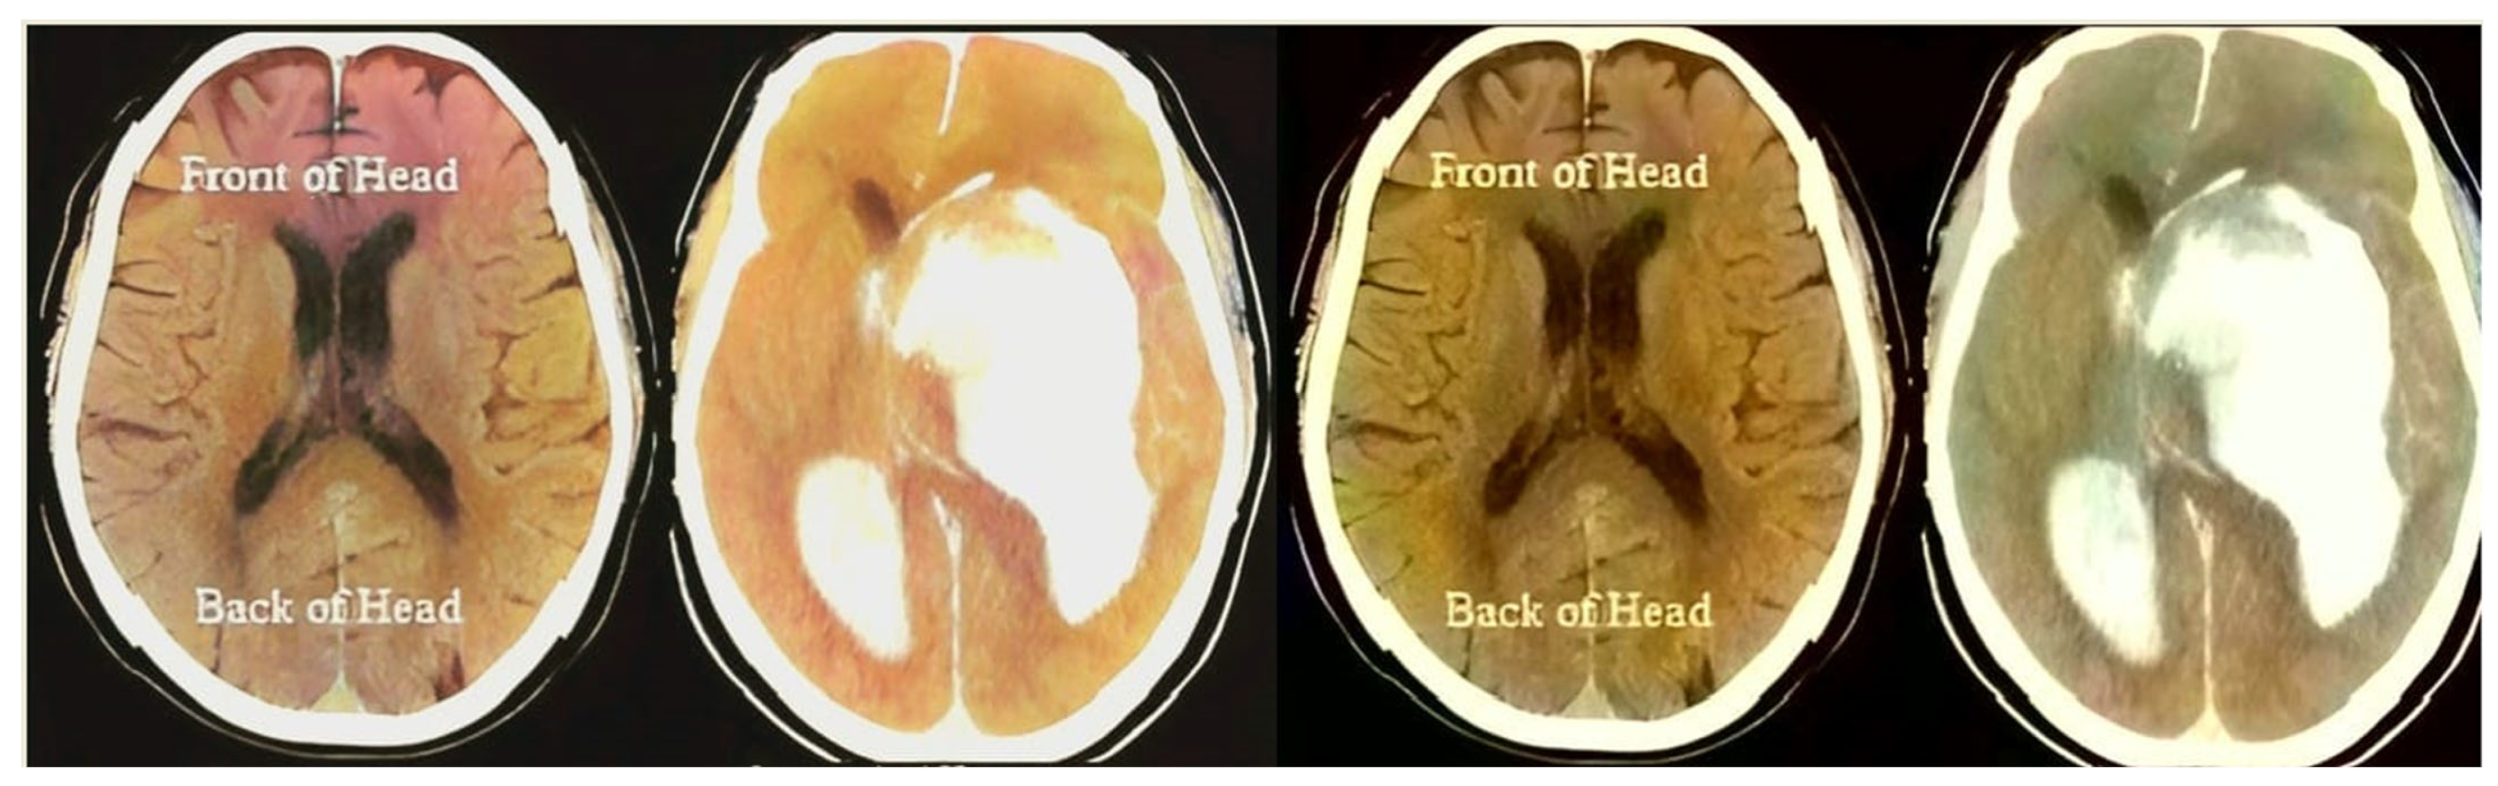

Figure 3.

Hybrid transformation and compression.

The “dwt2” method is used for the conversion. In the DWT process, the original image is decomposed into up to two levels using the “Haar” wavelet. This decomposition produces horizontal, vertical, diagonal, and proximity components. The decomposed components are reconstructed using the DIWT to recover the original image. This strategy is illustrated in Figure 2, and the compression method takes a decomposed image as input and compresses it using a wavelet packet compression technique using “Haar” wavelet packets. The compression method, “wpdencmp,” uses a soft thresholding technique that uses wavelet packets to compress the image and compute the threshold. This compression concept is illustrated in Figure 3, along with histograms of the original and compressed images. A step-by-step compaction process is shown in Figure 4. At each level, the images are refined, and the differences between levels are visible. The higher the number of coding levels of compression, the higher the image’s compression ratio and recovered energy. The compressed image is decompressed by wavelet packet reconstruction using the accounting matrix values of the decomposed image. Horizontal, vertical, diagonal, and proximity components are extracted from the decompressed image, and an IDWT is applied to recover the original image. A title image embedded in the patient data is visualized.

In Figure 3, the steganography image of the brain hemorrhage is taken, and DWT is applied. After compression, the compressed image is displayed as a bar graph. The wavelet reconstruction method recovers the compressed image from the compressed image. The target image is retrieved from the decompressed image by applying the IDWT method to the previous step. Figure 4 represents the DWT and IDWT of the brain hemorrhage image. A sample segmentation of the transformed image is also displayed.

Figure 5 represents the histograms of the steganography and decomposed and compressed images in red, blue, and pink colors, respectively. The obtained outcome shows that the adopted methodology is efficient regarding high-resolution lossless compression of medical images. In the resultant images, the novelty of the work is apparent; it can be seen that the proposed methodology enables excellent elaboration and enhancement using improved WTs and lossless compressions. Figure 6 represents the transition steps of the wavelet packet compression technique, where the images are clearly distinguished from one another.